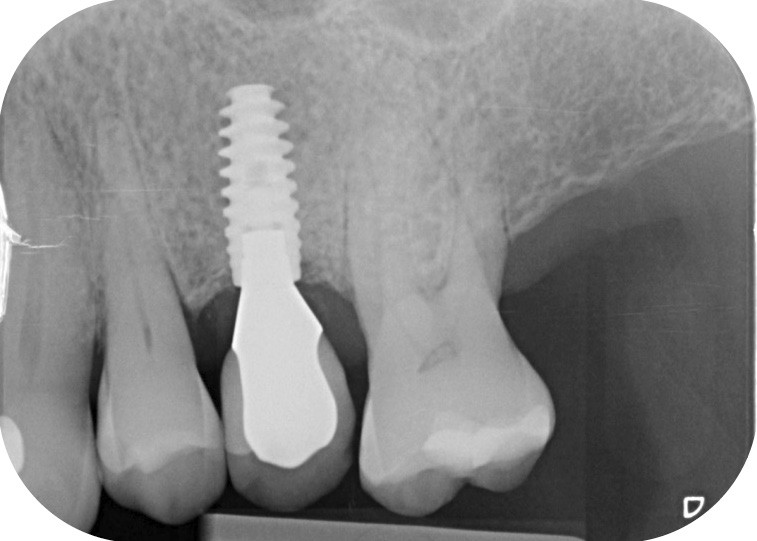

13 et 14. À 3 ans, une régénération osseuse satisfaisante et un bel aspect des tissus péri-implantaires sont observés. Les poches font 3 mm en mésial, distal et palatin, et 2 mm en vestibulaire. Il n’y a pas de saignement au sondage.